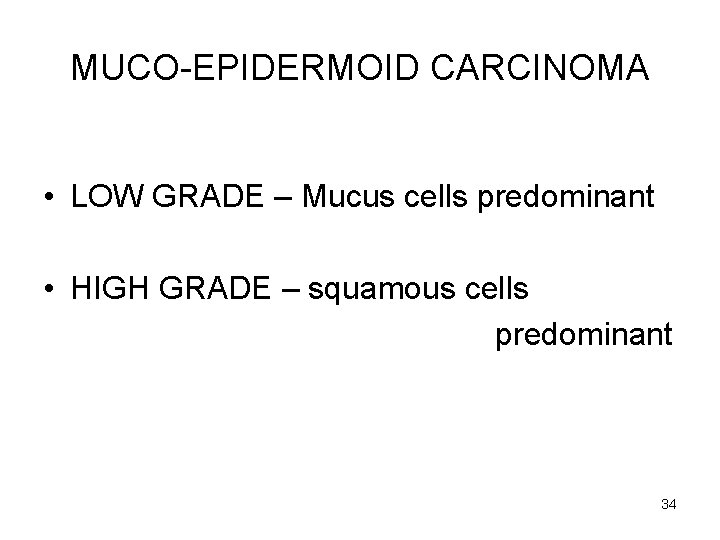

MUCO-EPIDERMOID CARCINOMA • LOW GRADE – Mucus cells predominant • HIGH GRADE – squamous cells predominant 34